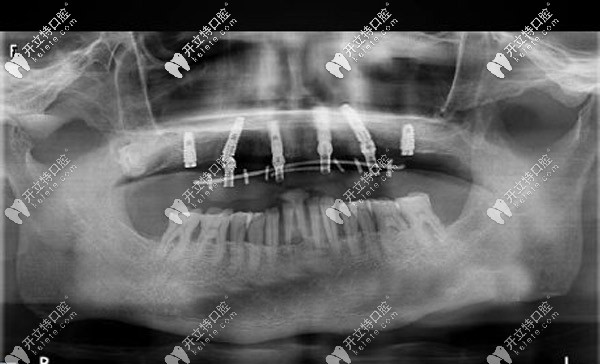

經過口腔CT三維拍片確診,周老先生患有牙周炎,且有牙齦萎縮的情況。羅緣口腔的種植醫(yī)生通過數(shù)字化動態(tài)導航系統(tǒng)在計算機上重建口腔頜骨三維立體模型。

與周老先生進行溝通后,確定了種植體嵌入位置、數(shù)量、種植深度、植體傾斜角度等等,并采用上頜6顆即刻種植技術,運用“數(shù)字化動態(tài)導航種植”方案。

口腔種植中的動態(tài)導航就像汽車導航一樣,在顧客進行種植牙手術時,可根據(jù)提前設計好的種植方案,通過顯示屏實時直觀地看到種植體植入頜骨的全過程。

全程監(jiān)控種植位點、角度、深度,能夠避免損傷重要的解剖結構。這樣做可以節(jié)省大量的種植時間,縮短牙骨暴露在外的時間,保存了牙骨的活性,有利于植體和牙槽骨的緊密結合。